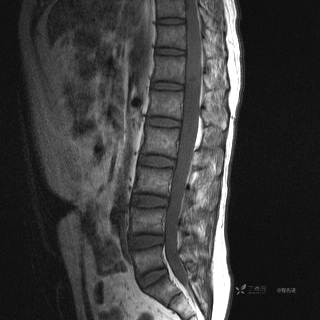

MR

T1